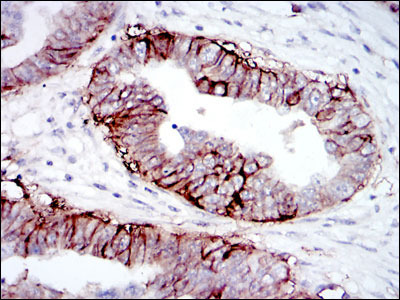

Supportive validation

- Submitted by

- Aviva Systems Biology (provider)

- Main image

- Experimental details

- Immunohistochemical analysis of paraffin-embedded ovarian cancer tissues using IGF1R mouse mAb with DAB staining.